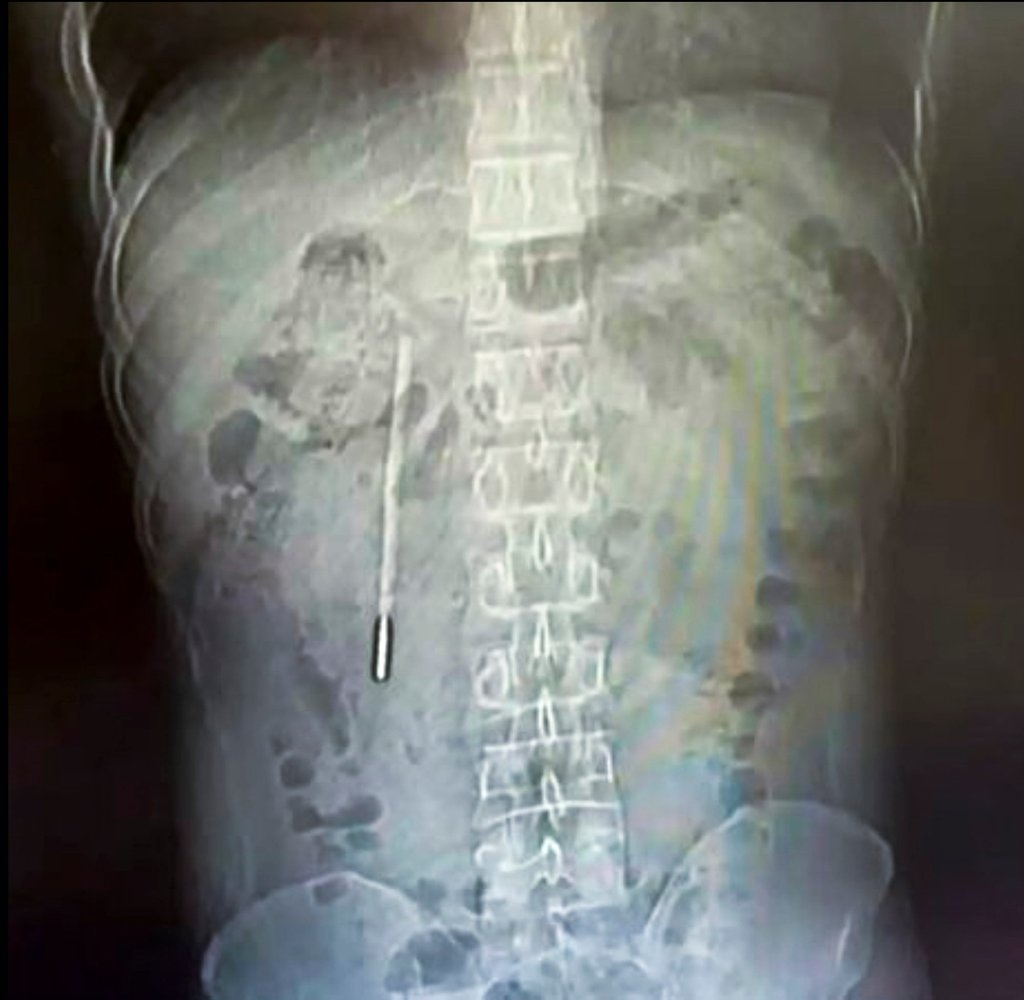

Theo kết quả từ các biện pháp chẩn đoán hình ảnh và chụp chiếu, các bác sĩ chuyên khoa đã phát hiện một dị vật nằm sâu bên trong tá tràng của bệnh nhân. Căn cứ vào hình dáng và đặc điểm trên phim chụp, đội ngũ y tế đã đặt ra nghi ngờ rất lớn rằng vật thể lạ này chính là một chiếc nhiệt kế thủy ngân.

Tình trạng lúc bấy giờ được đánh giá là vô cùng nguy hiểm. Phần đầu nhọn của chiếc nhiệt kế đang trong trạng thái ép trực tiếp vào lớp thành ruột của bệnh nhân. Vị trí và tư thế này đặt ra một nguy cơ cực kỳ cao về việc gây thủng ruột và dẫn đến tình trạng chảy máu trong nghiêm trọng, đe dọa trực tiếp đến tính mạng của người bệnh nếu không được can thiệp kịp thời.

Người đàn ông 32 tuổi họ Vương ở Ôn Châu, Trung Quốc phát hiện nhiệt kế thủy ngân trong tá tràng do vô tình nuốt lúc nhỏ.

Rất may mắn, thiết bị được lấy ra vẫn còn giữ được hình dạng nguyên vẹn ban đầu, mặc dù các vạch đo nhiệt độ in trên thân nhiệt kế đã bị mờ nhạt đi theo thời gian do tác động của môi trường dịch vị.